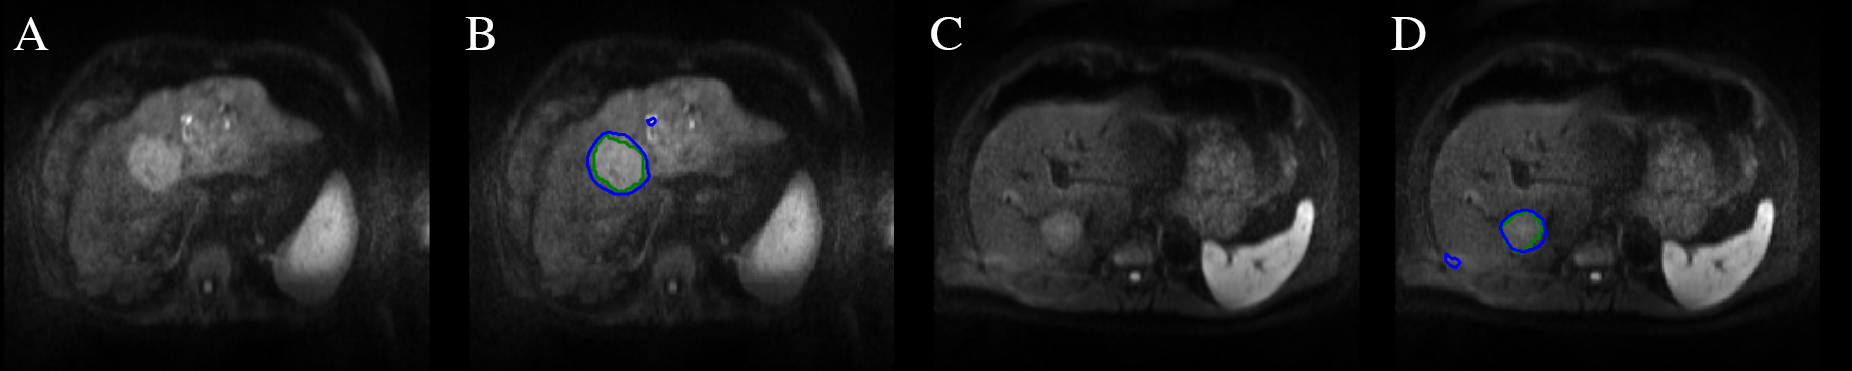

Refer to caption

Fig. 1: Results of the automatic HCC tumor segmentation in DW-MRI: A and C show the DW-MRI slice. B and D show the ground truth label of HCC in green and the automatic segmentation using CFCN in blue. The automatic segmentation algorithms successfully segments the HCC tumor in both cases. Only two small false-positive regions and a slight inaccuracy around the edges of the tumors are visible leading to a Dice overlap score of 85 % for B and 83 % for D. The patient in A/B belongs to class “high risk” whereas C/D belongs to class “low risk”. Yet, only subtle overall differences in appearance between the tumors are visible.

3.1 Qualitative

The qualitative results of the automatic segmentation are depicted in figure 1. The complex and heterogeneous shape of the tumor lesions was detected and segmented in both images using our automatic segmentation algorithm. The trained model achieves a Dice overlap score of 85% in both images. The segmentation reaches a high level of specificity by classifying all lesion pixels in the image as lesions. Small false positive outliers within the liver reduce the overall accuracy and Dice score.